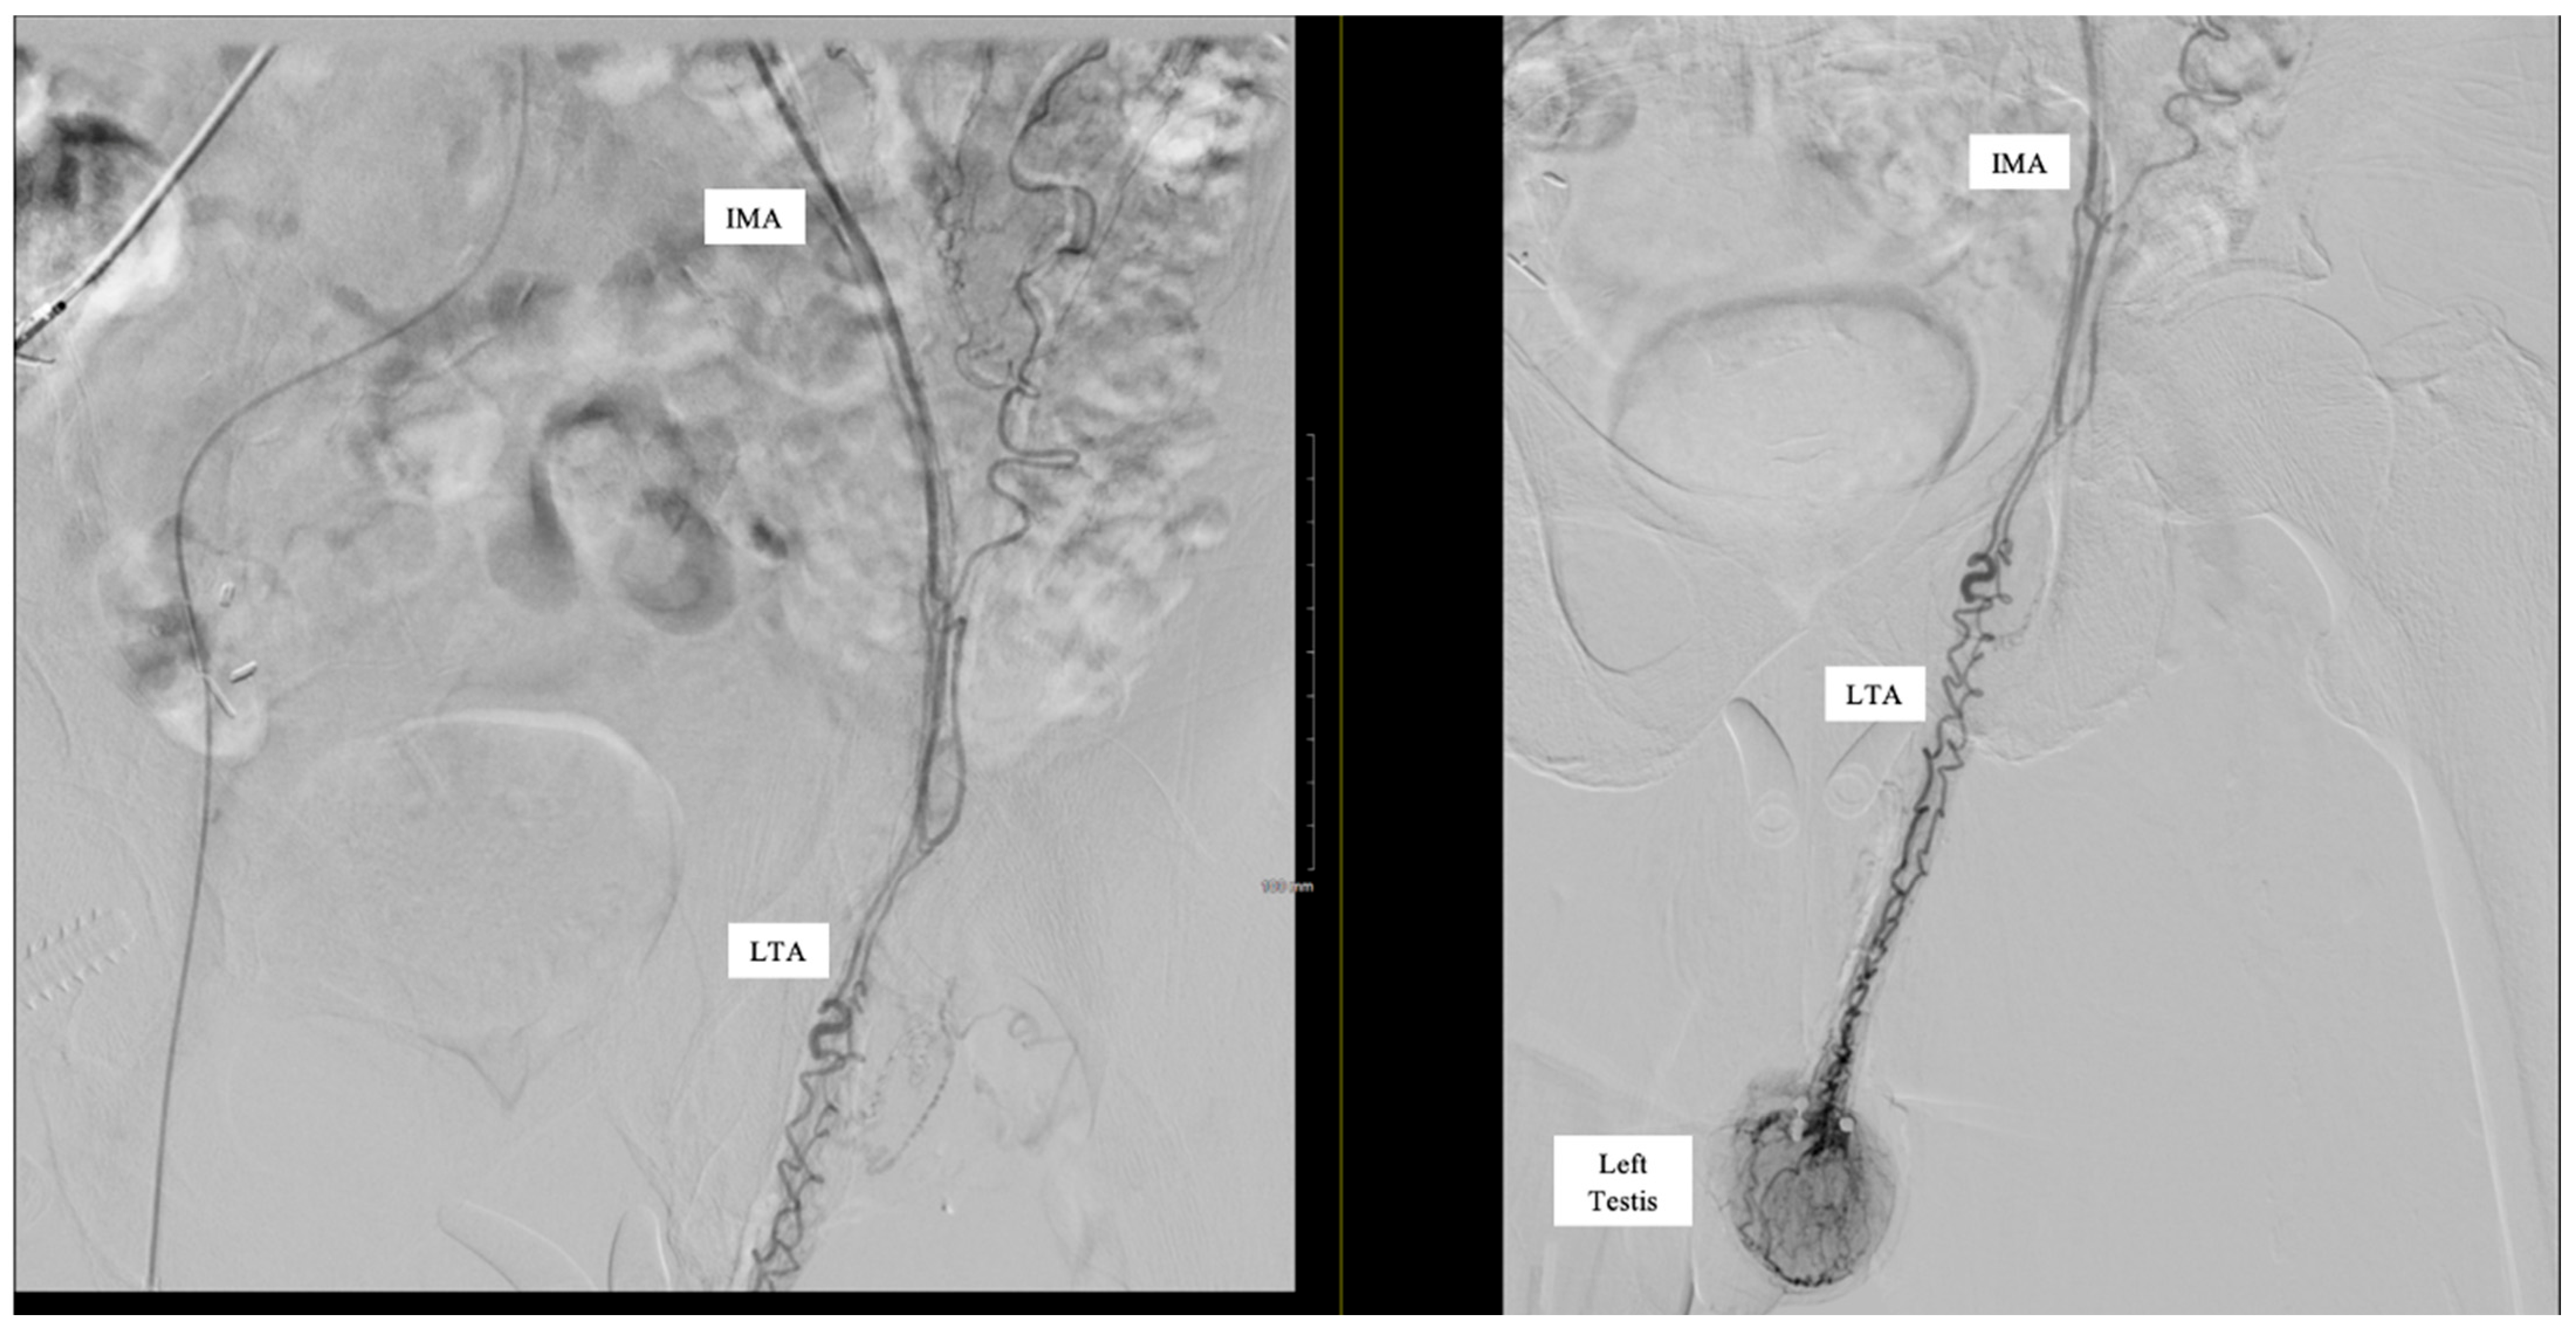

Subselective catheterization of the IMA was performed, and an angiogram demonstrated an aberrant LTA, shown in Figure 1. The sigmoidal branch was also identified; however, the superior rectal branch was absent from the IMA, as shown in Figure 2. Additionally, no active extravasation was identified. Selective catheterization of the artery supplying the sigmoidal distribution was performed, and Gelfoam embolization was performed prophylactically due to previous bleeding episodes involving the sigmoid distribution on the prior CT angiography (CTA). Postembolization arteriograms demonstrated sufficient occlusion.

Figure 1.

Inferior mesenteric artery (IMA) angiogram demonstrating accessory artery supplying left testis.